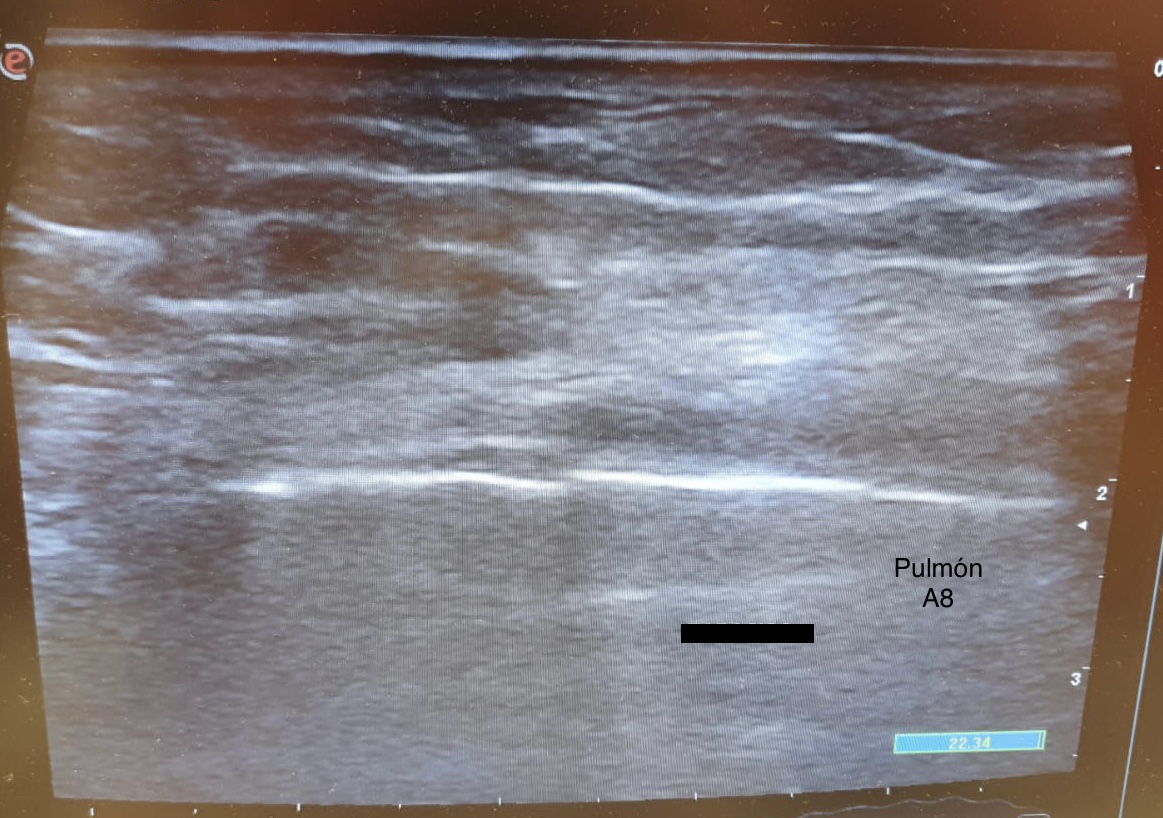

El examen eFast muestra sliding presente con línea pleural irregular y líneas B en la zona del traumatismo. Resto de zonas del examen negativas. La ecografía costal muestra imágen disrupción de la cara anterior de la cortical ósea de la séptima costilla compatible con una fractura costal.

La ecografía muestra una fractura con edema pulmonar focal secundario, sin otras complicaciones.

A las 48 horas el dolor estaba controlado con la medicación y el edema pulmonar se había resuelto.